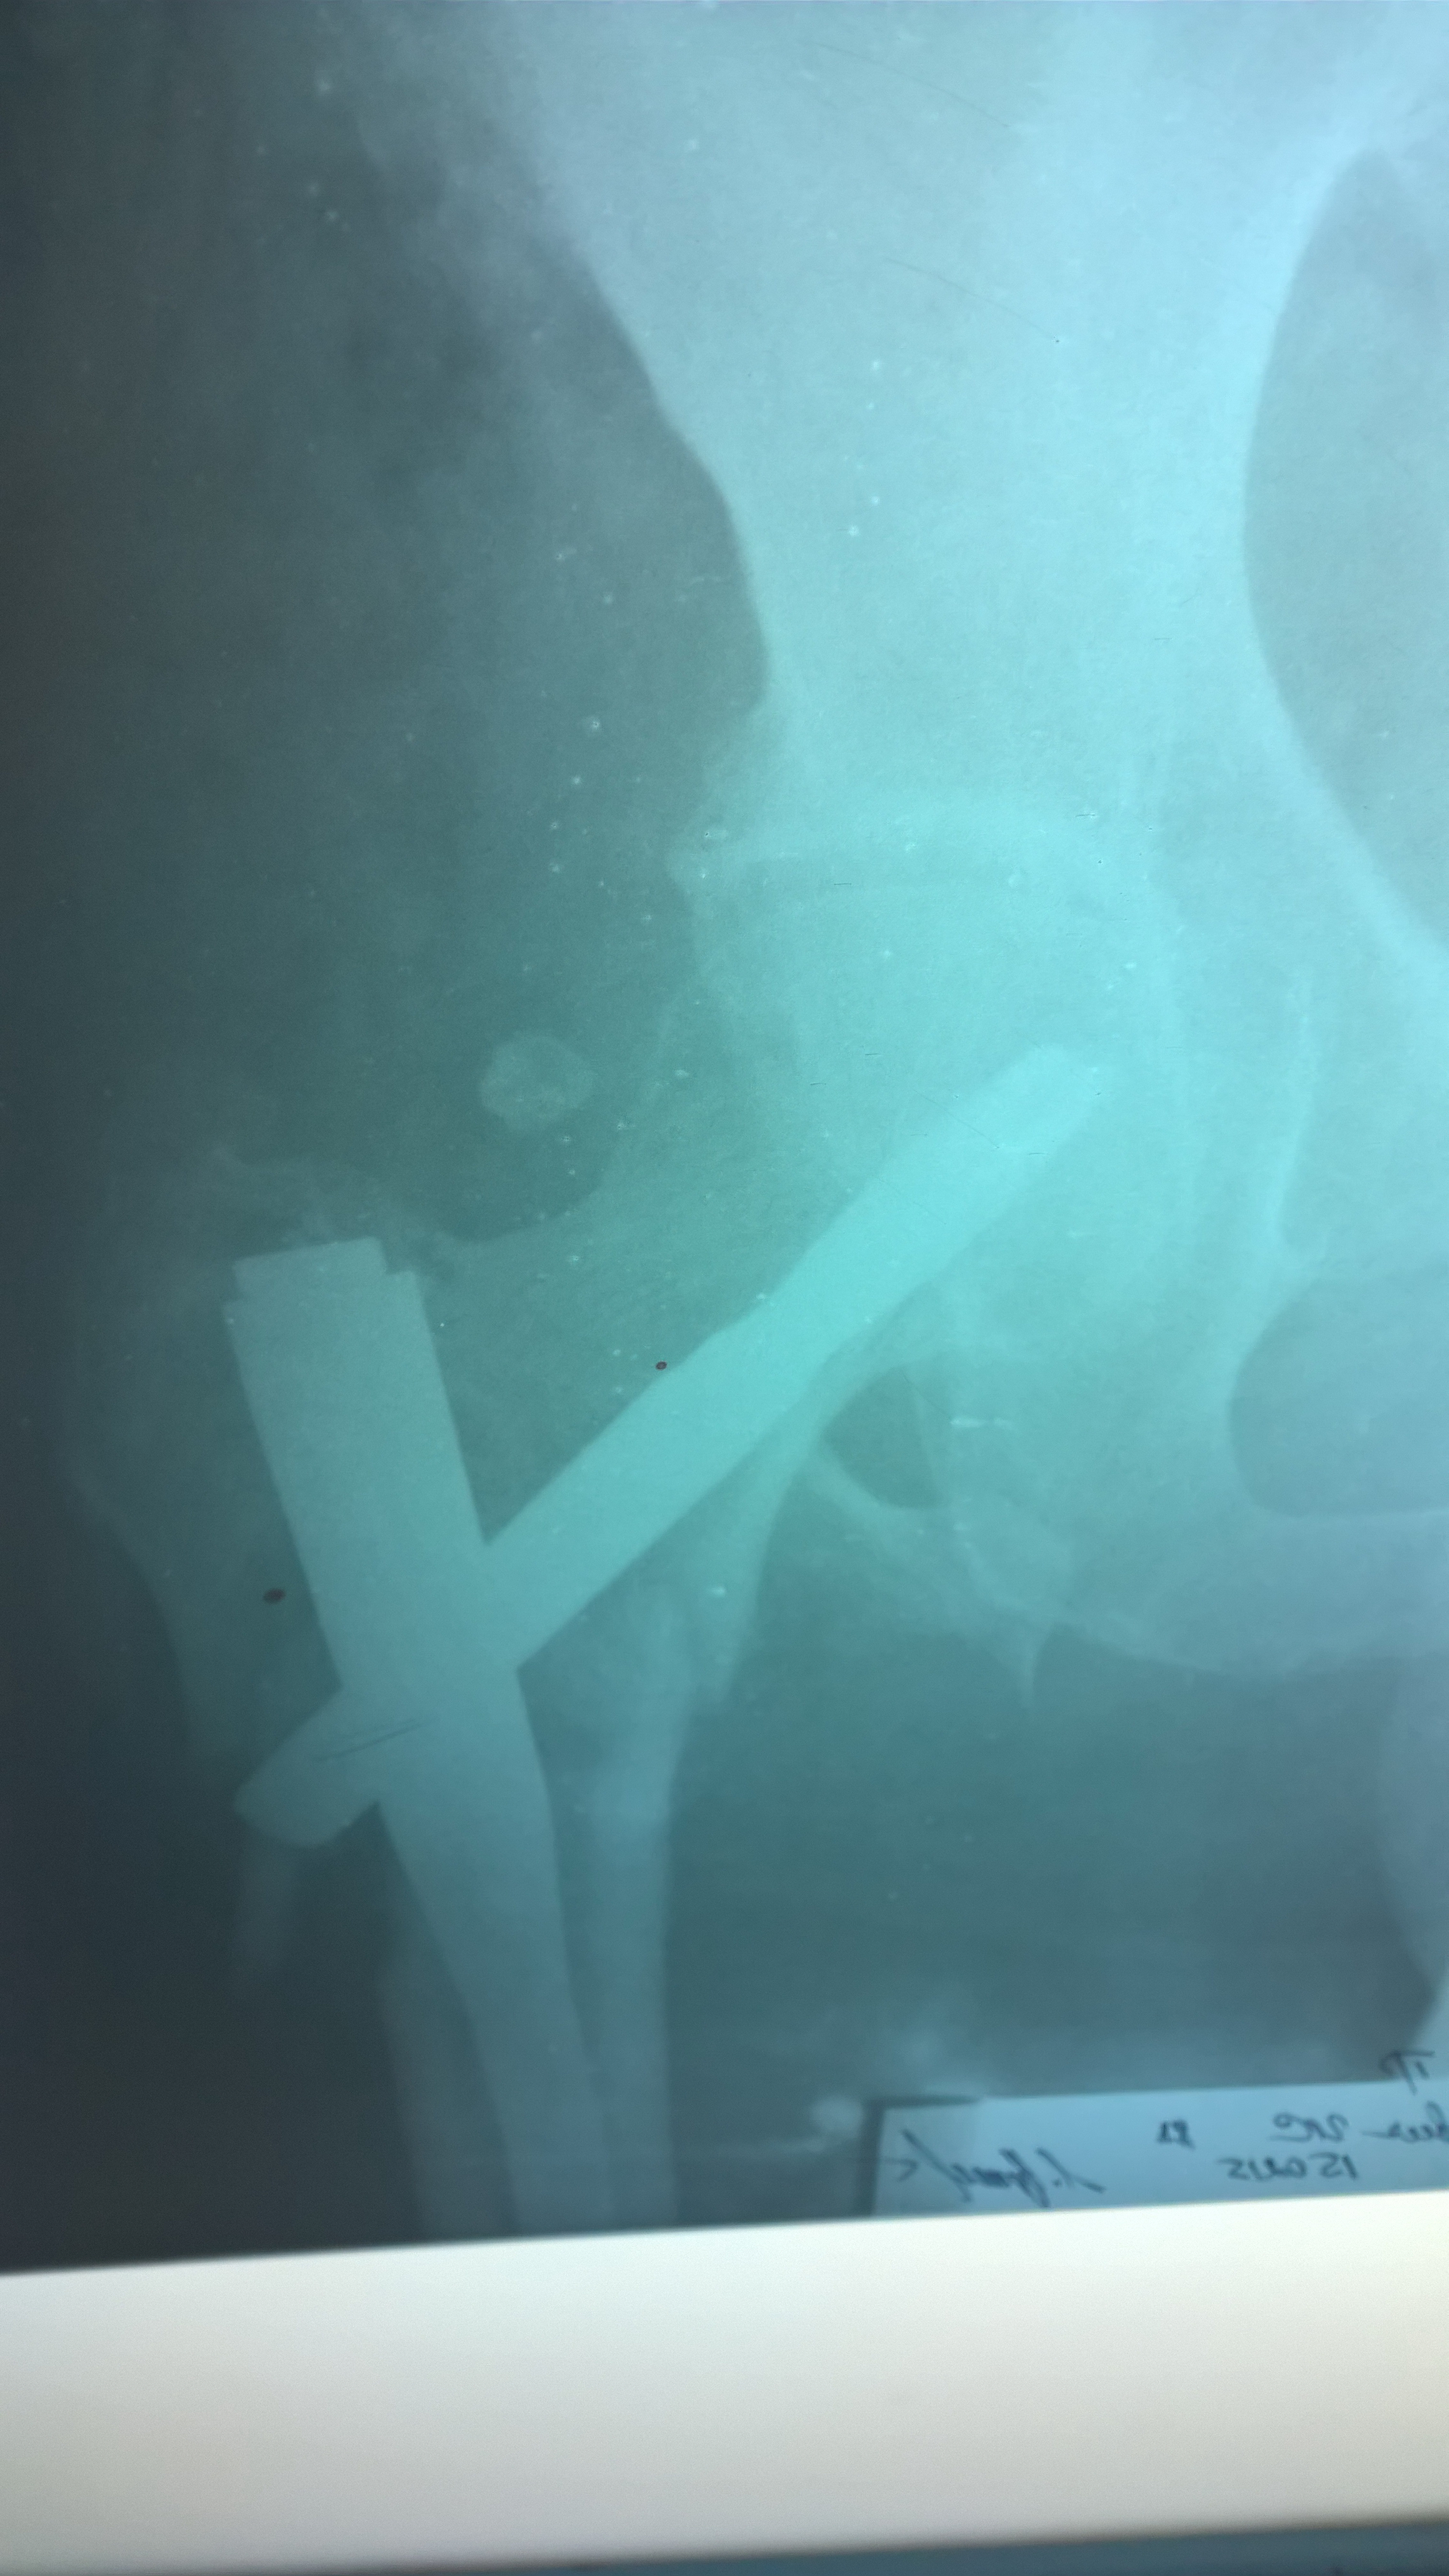

Современная методика лечения переломов бедренной кости - система PFNA (Proximal Femoral Nail Antirotation)